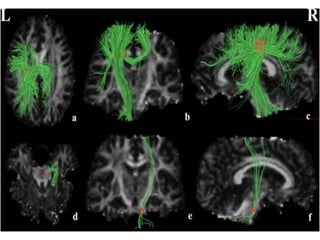

2. Diffusion-tensor imaging

• Diffusion-tensor imaging, structural neuroimaging

technique ,measures extent and direction of water

diffusion.

• Patients with ALS have been shown to have decreased

fractional anisotropy and increased mean diffusivity